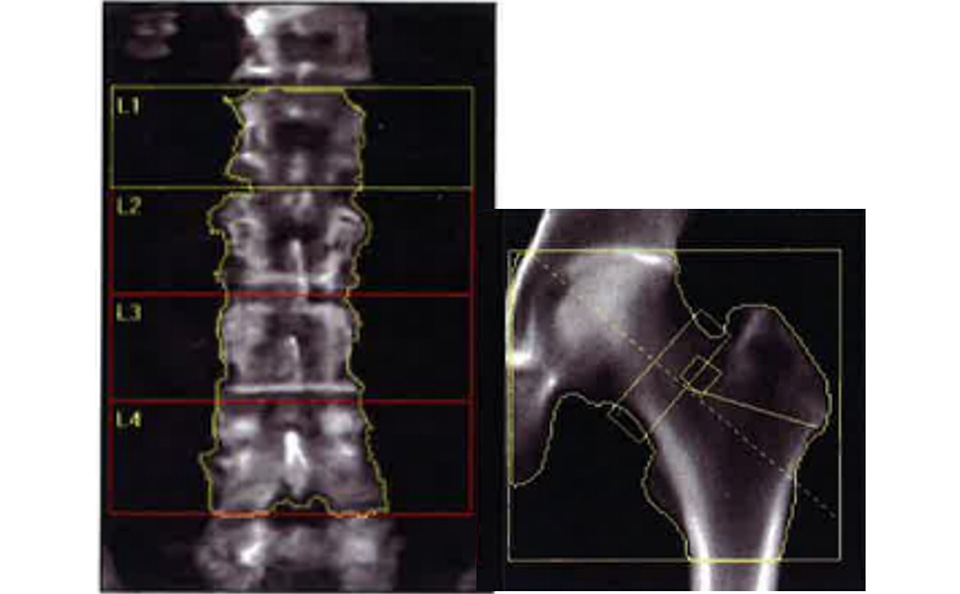

骨塩定量検査とは、骨組織の骨量が加齢と供に減少し、腰や背中の痛み・骨折などを起こしやすくなる骨粗しょう症の診断を主に行う検査です。X線を照射し直接骨量を測定するDEXA(デキサ)法で腰椎・大腿骨などを撮影して骨量を測定します。今年度(令和5年)、新たに東洋メディックの「Horizon」という装置を導入しました。これにより、今までよりも高精度な骨塩定量検査が可能となっています。

測定部位(右図:腰椎、左図:左大腿骨)

測定部位(右図:腰椎、左図:左大腿骨)